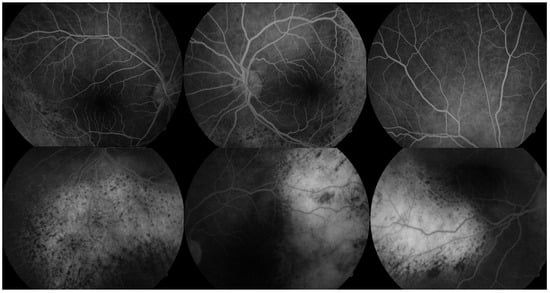

Ophthalmologic evaluation revealed normal intraocular pressure in both eyes. An anterior segment examination was unremarkable, with no signs of inflammation. A dilated fundus examination showed multiple ill-defined pigmented choroidal lesions, areas of retinal pigment epithelium mottling, and diffuse uveal thickening in both eyes (Figure 1). Distinctive orange-red subretinal patches were observed bilaterally, predominantly in the posterior pole and peripapillary regions. No intraocular mass or signs of active inflammation were noted. Both lenses were clear at presentation, with no signs of cataract formation noted on slit-lamp examination.

Figure 1. Color fundus photographs of both eyes demonstrating suggestive features of BDUMP in a 64-year-old patient with chronic myelomonocytic leukemia. Top row (posterior pole and optic disc views): Multiple ill-defined orange-red subretinal patches are observed, predominantly in the peripapillary and inferior posterior pole regions. RPE mottling is evident, with preserved foveal contour corresponding to stable central vision. Bottom row (mid-periphery and inferior retina): Subtle RPE irregularities are visible, including areas of pigment clumping and scattered lipofuscin-like deposits. Diffuse choroidal thickening and subretinal alterations contribute to the early ‘leopard-spot’ pattern suggestive of BDUMP.